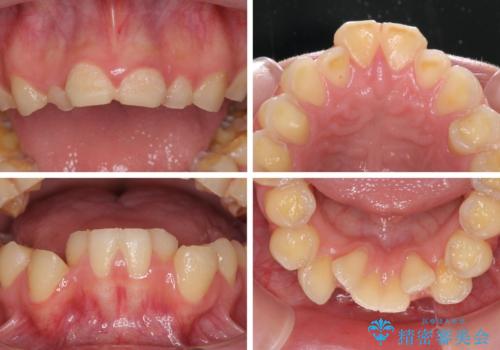

- 一時期の拒食症に伴い歯が酸で溶けてボロボロになってしまったとのことで来院された患者様です。

酸によりエナメル質の大半が溶けており、下顎前歯以外は酷いむし歯のような状態でした。

当初はほとんどの歯をむし歯治療のようにオールセラミッククラウンにて補綴治療を行う予定でしたが、仮歯に置き換えた時点で、口元の突出感や下顎前歯の叢生が気になるとのことで、上下左右の第一小臼歯4本を抜歯したワイヤー装置での抜歯矯正を行うこととしました。

矯正治療終了後に、残った歯をオールセラミッククラウンにて補綴治療を行うこととしました。

途中来院が困難な時期があったり、歯周外科処置を行って治癒を待ったりと、治療期間は長くなりましたが、初診時とは比べものにならないくらいきれいに仕上げることができました。